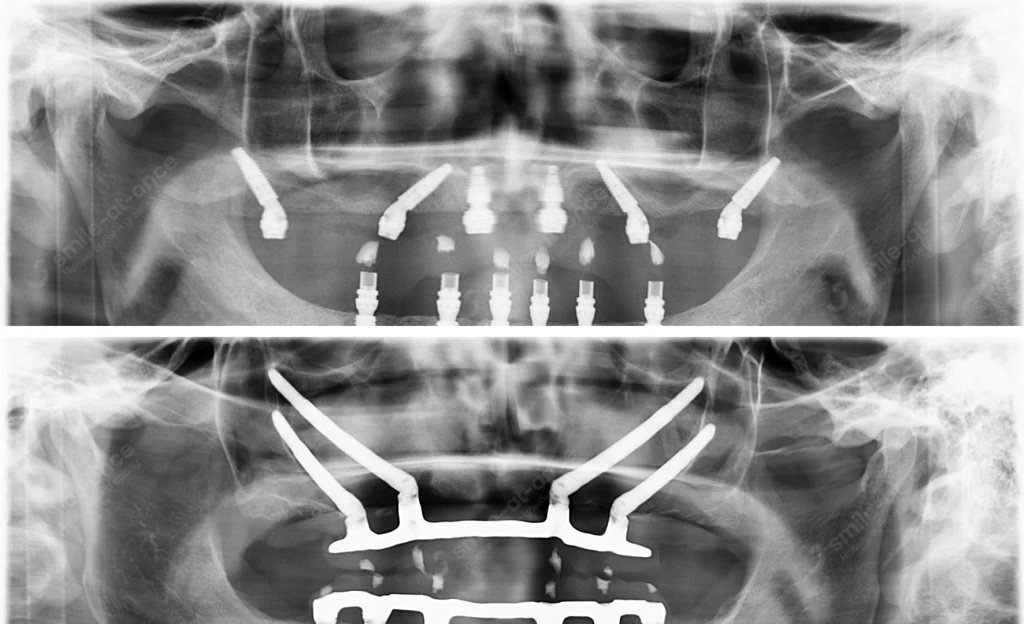

Начинаю с расширенной диагностики: КТ/3D, фото-протокол, цифровой анализ прикуса. Мы разбираем причины — от гигиены и прикуса до системных факторов. И только после контроля воспаления (или стабилизации дистрофии) обсуждаем имплантацию.

- Навигационная хирургия и 3D-планирование — заранее «примеряю» импланты к вашей анатомии, операция идёт короче и бережнее, протез — точнее.

- План имплантации. 3D-моделирование, навигационные шаблоны, согласование эстетики будущих зубов.

- Хирургия. Удаляю безнадёжные зубы и ставлю импланты. Если достигаю первичной стабильности — делаю немедленную нагрузку при пародонтозе: адаптационный мост в 1–3 день.

- All-on-4 / All-on-6 / Pro Arch — когда собственные зубы уже «не держат оборону»: надёжная несъёмная опора на 4–6 имплантах с быстрым прикусом. Это несъёмные мосты на 4–6 имплантах с немедленной нагрузкой.

- Скуловые импланты (Zygoma) — при выраженной атрофии верхней челюсти, когда наращивать кость долго и рискованно; дают шанс поставить зубы за 2–3 дня.

Кейc Б. Нижняя челюсть, выраженная убыль кости, All-on-6 с немедленной нагрузкой

Сценарий: костная поддержка снижена, выбираем шесть имплантов для равномерного распределения нагрузки. Адаптационный каркасный мост — на 3-й день.

| Хирургический этап: All-on-6 (немедленная нагрузка) | от 235 000 руб. | С установкой 6 имплантов |